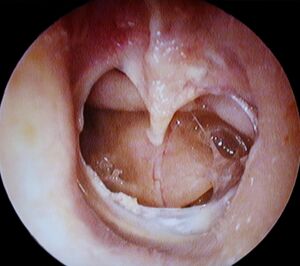

شق طبلة الأذن (Q54608)

an injury leading to a hole in the eardrum الإنجليزية

image الإنجليزية